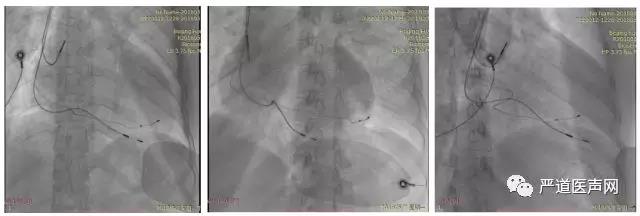

手术过程:

行冠状静脉造影后选择侧静脉为靶血管,经腋经脉植入电极导线,心房电极植入右心房心耳,右心室电极植入中低位室间隔,左室电极植入冠状静脉侧分支,术中测试左心室阈值2.5V,感知15mV,阻抗680Ω;右心室 阈值0.75V,感知20mV,阻抗580Ω。出院后心电图显示QRS波时限138ms。 CareLink远程随访显示患者动态BIV起搏比例99%,AV间期一直动态优化,术后5个月心脏超声提示EF 52%,几乎与正常人相同。5个月后患者回医院随访,自述目前心功能明显改善,可以正常生活,饮食睡眠良好,期间没有因为心衰再住院治疗。

分别为:造影、AP、LAO45°

术者总结:

AdaptivCRT可以通过患者活动度和传导情况自动优化起搏间期。